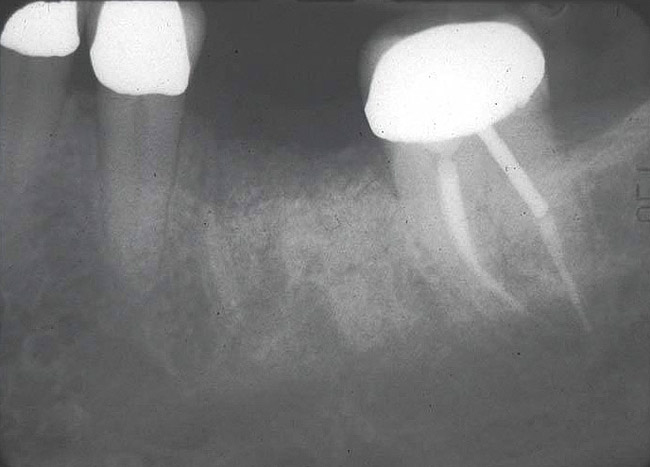

If the most crestal aspect of the interradicular bone is at least 3-mm-wide mesio-distally: A 2.2-mm-wide guide bur is drilled to the appropriate length, a guide pin is inserted, and a radiograph is taken (Figure 7). If necessary, the initial osteotomy is extended apically. A tapered osteotome is inserted into the osteotomy and moved mesio-distally and bucco-lingually to expand the osteotomy site. A 2.8-mm bur is used to prepare the osteotomy to depth, and a 2.8-mm-wide tapered osteotome is inserted in the osteotomy and once again utilized in mesio-distal and bucco-lingual directions to expand the osteotomy site. If the mesial and distal aspects of the interradicular bone are still intact at this point, a 3.5-mm bur is utilized to prepare the osteotomy to depth. A 3.5-mm-wide osteotome is inserted into the osteotomy and utilized in the manner already described. A decision is made as to whether to place a tapered implant with a 4.1-mm-wide base and a 6.5-mm-wide neck, or to use a 4.8-mm-wide bur and prepare the osteotomy to depth, in anticipation of placement of an implant with a 4.8-mm-wide parallel wall body and a 6.5-mm-wide platform. The chosen implant is inserted into the osteotomy (Figure 8), appropriate regenerative materials are placed, and the flaps are sutured. Following maturation of the regenerating hard tissues, the implant is ready for restoration (Figure 9). A radiograph taken 54 months after implant restoration demonstrates stability of the peri-implant crestal bone (Figure 10).